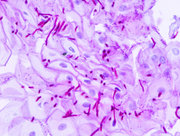

يتم أخذ مسحة من المنطقة المصابة بداء المبيضات، ويتم دهنها على طبق الزرع ويحضن على حرارة 37 درجة مئوية لعدة أيام، و يكن من لون و شكل طريقة نمو المستعمرات أن تساعد على التعرف على الكائن الحي الموجود في المنطقة المصابة. هذه الطريقة أقل استعمالاً من الفصح الميكروسكوبي نظراً إلى أنها تستغرق وقتاً طويلاً كما أنها حساسة جداً و يمكن للعينة أن تتلوث مما يجعلها غير مفيدة في التشخيص.